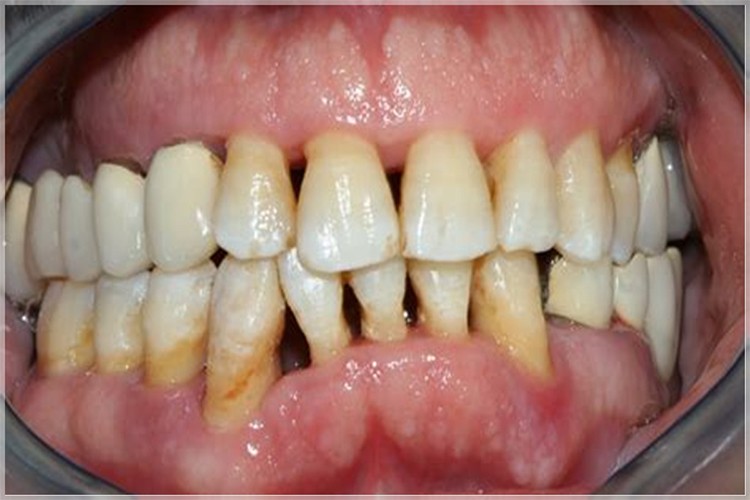

Diş eti çekilmesinin, diş eti kenarının kök yüzeyine doğru geri çekilmesi durumuna denildiğini ifade eden Dr. Öğr. Üyesi Kübra Karaduran, “Bu durum diş kökünün açığa çıkmasına neden olur. Diş eti çekilmesine neden olan faktörler arasında; diş pozisyon bozuklukları, yanlış teknikle veya sert diş fırçalama, diş sıkma, kötü ağız hijyeni ve diş eti hastalıkları yer alır.” dedi.

Diş eti çekilmesi ile dişin kök kısmının açığa çıkmasının bu bölgede bakteri birikimini kolaylaştırdığına dikkat çeken Karaduran, “Zamanla, bakteri plağı ve diş taşı birikimi sonucu oluşan diş eti hastalığı nedeniyle dişi çevreleyen kemik yapısı etkilenir, kemik kaybı yaşanabilir ve dişlerin destek yapısı zayıflar. Diş eti çekilmesi tedavi edilmediğinde ve dişleri çevreleyen sert dokunun tamamen ortadan kalktığı durumlarda süreç dişin kaybı ile sonuçlanabilir.” şeklinde konuştu.